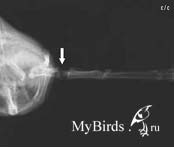

Пациент после операции: Интрамедуллярный остеосинтез сломанной лучевой кости с помощью внутрикостной спицы (ВК спица, стрелка: выход штифта). Photo: C. Haupt

Перелом лучевой кости, смещенный

Перелом лучевой кости после внутрикостной фиксации 0,4 мм канюлей |

Перелом лучевой кости |

- покой, возможна крестообразная повязка; - только если нет смещения; - часто неудовлетворительно из-за смещения |

Интрамедуллярный остеосинтез, внутрикостная спица остается 10 дней |

Последующая физиотерапия |

По возможности предпочтение нужно отдать хирургическому лечению переломов, если дело касается стрижей. Внутрикостная фиксация доказала свою эффективность во многих случаях, проводится быстро и легко и причиняет меньше всего неудобства для пациента во время выздоровления. Во время операции ни в коем случае не должно пострадать оперение. После удаления внутрикостной спицы необходимо в течение нескольких дней проводить физиотерапию.

Относительно частые переломы лучевой кости, которые при отсутствии лечения могут привести к ограниченной возможности полета, скрепляются с помощью 0,4 мм канюли, вставляемой в дистальный конец перелома. Канюля выходит через головку лучевой кости, определяемой пальпацией в плечевом суставе, и проталкивается в обратном направлении в проксимальный конец перелома до тех пор, пока не окажется прямо перед локтевым суставом. Спица, выходящая из плечевого сустава, должна на 1-2 мм выходить из кожи; конец спицы необходимо закрыть небольшим кусочком пластыря, чтобы пациент не смог ее вытянуть.